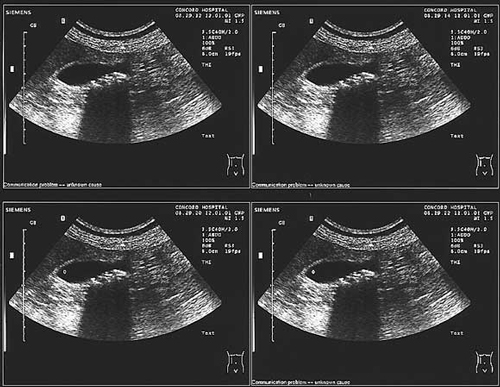

Fishy gallbladder

Med J Aust 2002; 177 (11): 672. || doi: 10.5694/j.1326-5377.2002.tb05008.x